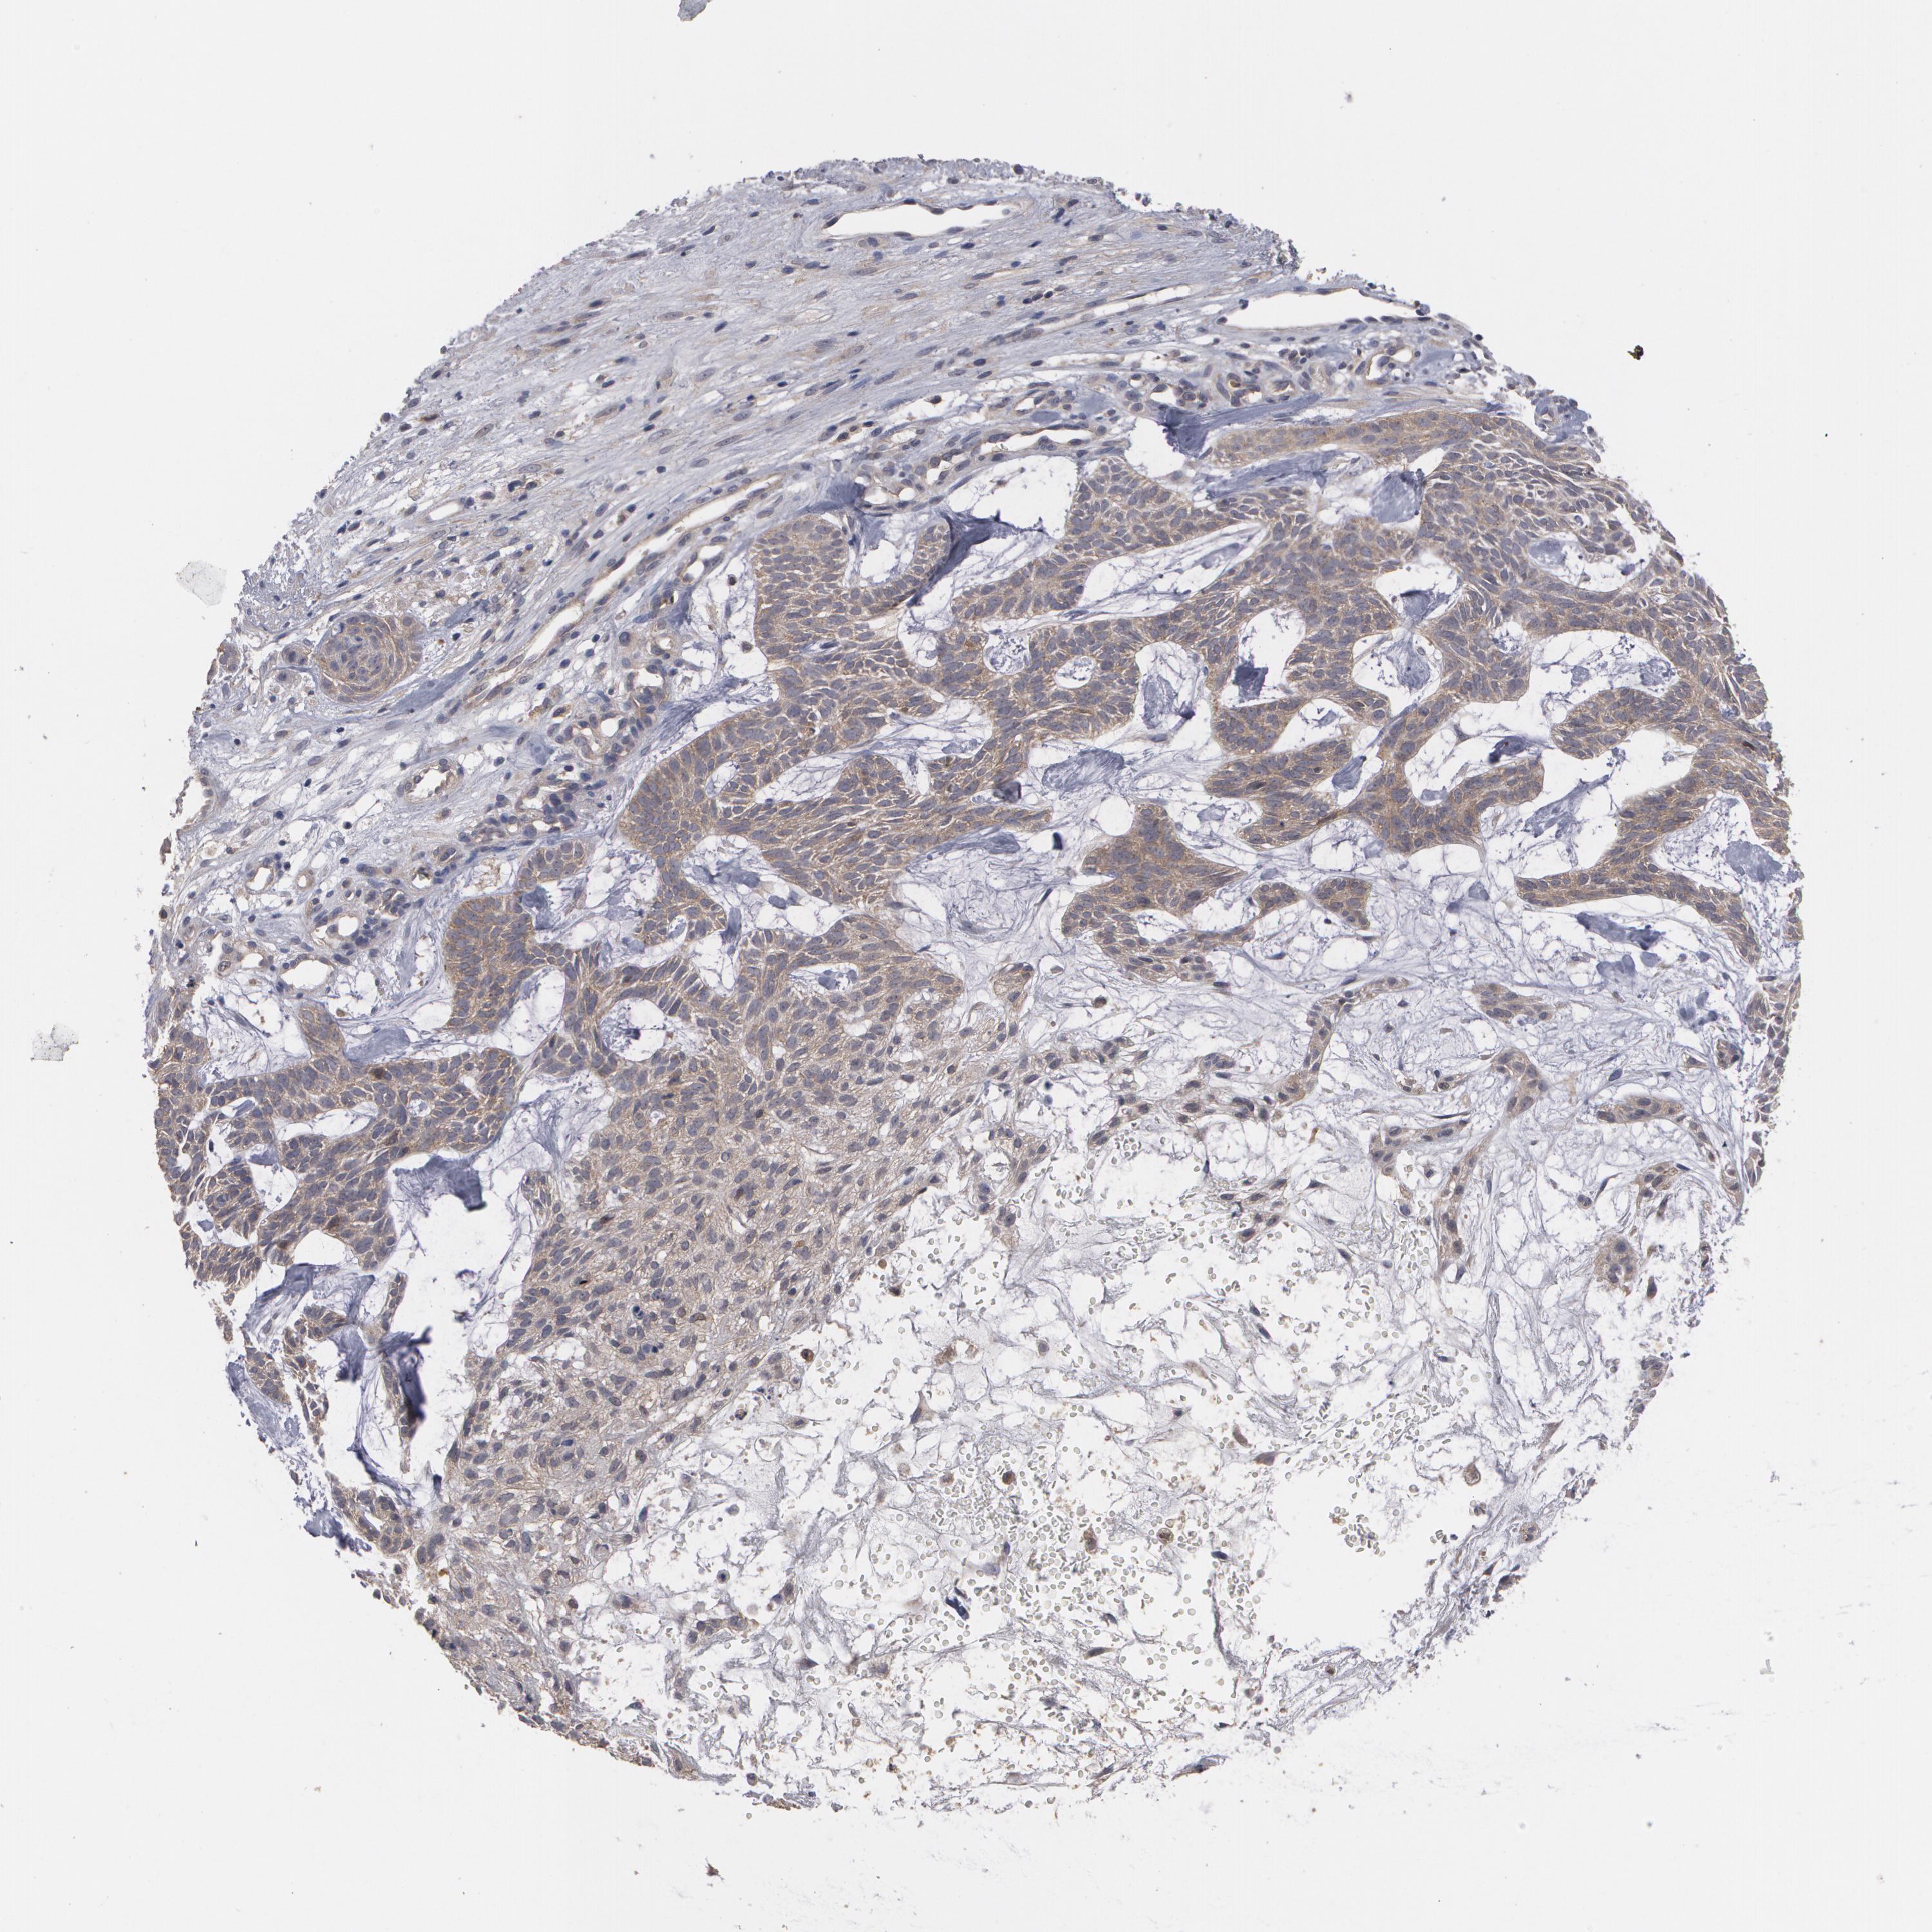

SKIN CANCER - Protein expressioni

A mouse-over function shows sample information and annotation data. Click on an image to view it in a full screen mode. Samples can be filtered based on level of antibody staining by selecting one or several of the following categories: high, medium, low and not detected. The assay and annotation is described here.

Each image is clickable and will lead to virtual microscopy that enables deeper exploration of all samples and also displays staining intensity scores, fraction scores and subcellular localization as well as patient and tissue information for each sample.

Antibody HPA026114

Antibody HPA051524

Antibody CAB002756

Staining

High

Medium

Low

Not detected

Intensity

Strong

Moderate

Weak

Negative

Quantity

>75%

75%-25%

<25%

None

Location

Nuclear

Cytoplasmic/membranous

Cytoplasmic/membranous,nuclear

Basal cell carcinoma

Squamous cell carcinoma, NOS

Squamous cell carcinoma, metastatic, NOS